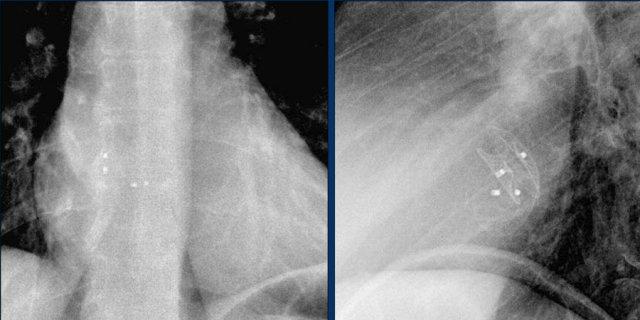

Đây là ví dụ về một ICD với các điện cực đặt tại tiểu nhĩ phải, mỏm thất phải và một điện cực đến thất trái qua tĩnh mạch vành sau.

Có thể nhận biết hai cuộn sốc điện của ICD dưới dạng các dải trắng dày hơn dọc theo đường đi của điện cực.